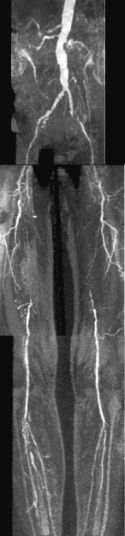

CE-MRA of the aortic arch and great vessels (left) into the brain, renal arteries (top), selective carotid bifurcation (top right) showing ICA/ECA stenosis, and 3-section run-off (very right) showing multiple stenoses, including long-segment bilateral SFA stenoses.